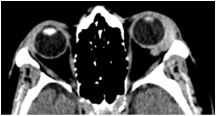

Orbital CT imaging revealed an infiltrative hyperdense lesion in the left lacrimal gland, encircling the globe, the muscle cone and the lateral and proximal portions of the optic nerve, without invading any of these structures, nor the extraocular muscles or the orbital walls (Figure 1 [Fig. 1]). On ocular ultrasound the lacrimal gland lesion exhibited well defined borders, internal homogeneous structure and medium/low reflectivity.

Figure 1: Orbital CT, axial view shows an infiltrative lesion, located in the left lacrimal gland.